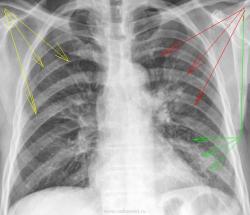

Мужчина обратился в приёмное отделение с жалобами: кашель с трудноотделяемой мокротой , повышение температуры тела,одышку, сухость во рту, общую слабость. Направлен к нам с предворительным диагнозом: пневмония, под вопросом. Из анализов ОАК Нb г/л 158 , СОЭ мм/ч  19.0 , Лейкоциты 8.9 , Эритроциты  4.74.

Пневмония справа на уровне 3 р, медиально, по типу перициссурита. Болше ничего не нашел.

Есть ещё в базальном отделе слева, прозрачность снижена.

За сердцем что ли? Возможно, но я бы хотел уточнить левым косым и/или боковым. Может просто сосуды так выглядят?

Меня учили обращать внимание на чёткость контуров диафрагмы.

В.Б. Серов: "Пневмония справа на уровне 3 р, медиально, по типу перициссурита. Болше ничего не нашел."

v1tal: "Есть ещё в базальном отделе слева, прозрачность снижена."

А что слева в прикорневой области?

Да, Валентин Львович, это тоже я расчитал как инрестециальные проявления.

Мы, конечно можем предполагать, что это усиление или обогащение легочного рисунка, высказывать предположение, что это "пневмонические изменения" или перисциссурит и т.д. и т.п., но без боковой проекции - это увы только предположения или рассуждения. Нужна боковая - боковые.

Конечно соглашусь с Валентином Львовичем. Без боковых можно только предполагать. Но скорее всего пневмония в S6 и S10 слева. Десятый сегмент слева, как раз за тенью сердца.